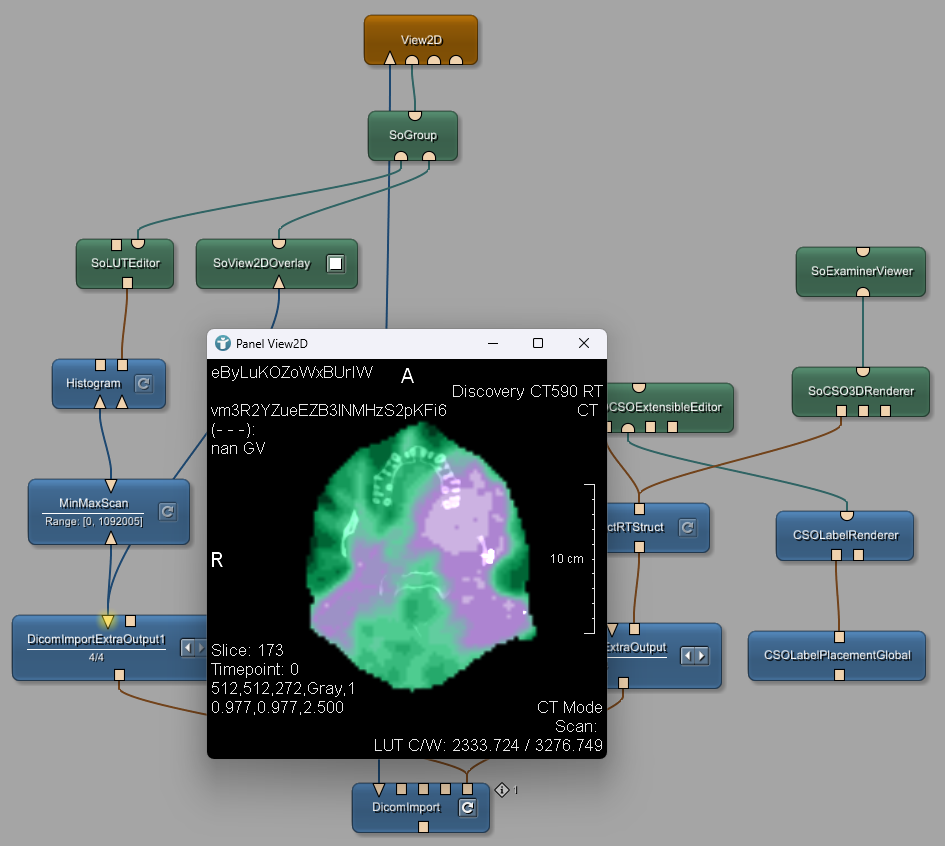

![Best DICOM Annotation Tools for Radiology AI [2024 Review]](https://images.prismic.io/encord/b3ed70f7-f029-42be-b3ec-bfbe9dd17669_MONAI+-+DICOM+annotation+tools.png?auto=compress,format)